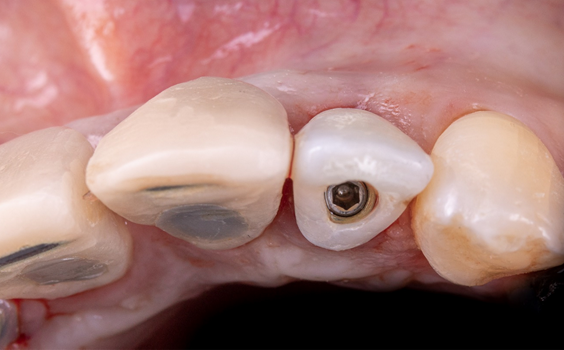

Exodontia atraumática dos elementos 12 e 22, com uso de periótomo e fórceps, instalação imediata do implante Cone Morse “Due Cone” Implacil 3.5×11. Para perfuração inicial, foi utilizada a técnica do approach palatino e, ao final do processo de fresagem e instalação, obteve-se uma carga primária de 45 newtons, a qual nos permitiu ter segurança para instalação do pilar Ideale, com medida 3.5×3.5×4.

O provisório foi realizado utilizando o próprio dente da paciente. Após ajustes iniciais para adequação, tal qual remoção da porção radicular e esvaziamento interno do elemento, capturamos o dente utilizando resina flow sobre o componente de provisório de 4mm do Ideale, deixando-o sem nenhum contato em desoclusão. O preenchimento do gap foi realizado com hidroxiapatita bovina 75% e colágeno tipo 1 25%(Extra Graft).